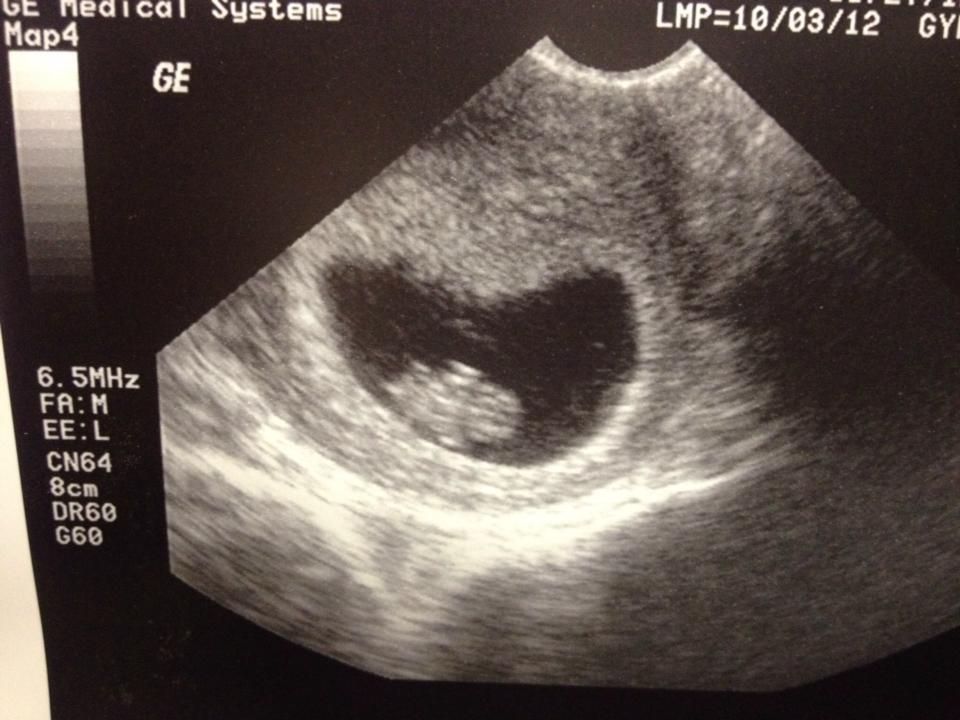

We are thrilled to be welcoming our third child to our little family this March! Much like her older sister, this little girl is already enjoying surprising mommy & daddy. While unexpected, she is very much wanted and we cannot wait to meet her!

Pregnancy is a weird experience. I suppose it is magical and amazing but mostly, I find it strange. Each pregnancy has been different, however there is a consistent theme in mine…fear of the ultrasounds.

Depending on who you speak with, some parents will tell you that once they had a child with special needs, they were too scared to have more children. Others state that they never gave it any thought and some say they would proceed but in a half terrified state. I fall somewhere in between category two & three. We wanted more than one child and Lily, being our first, and having Down syndrome really did not deter us much from having additional children. What it did do, was create an innate fear within us when it was time for the anatomy scan ultrasound.

The biggest difference in this pregnancy is that I decided to have a prenatal test done. This test would clue us in on any abnormal chromosomal activity. So effectively, we would know when I was barely 10 weeks if there was a chromosomal abnormality present. (As a big bonus, we also would learn the gender of our baby!) Every pregnancy is scary so I decided to shed some light on some of the fear so that I could begin to let go and revel in this one.

Now we still have that big, scary anatomy scan coming up in a couple of weeks. I have chosen to not care anymore. Those thoughts will come and go and eventually will fade back into the recesses of my mind where I prefer them to reside anyway. Soon we will welcome our little girl. She will meet her big sister and big brother and all will be right with our little world, no matter who she is and who she will become. ❤